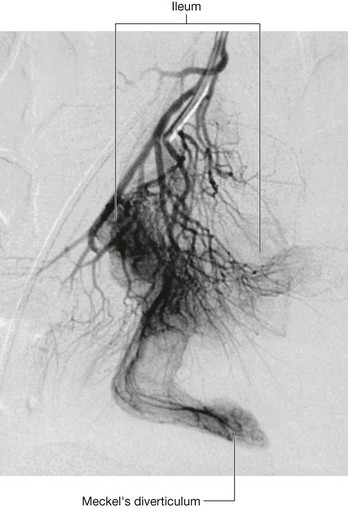

The midgut develops into the distal part of the duodenum, the jejunum, ileum, ascending colon, and proximal two-thirds of the transverse colon. A small yolk sac projects anteriorly from the developing midgut into the umbilicus.

Rapid growth of the gastrointestinal system results in a loop of the midgut herniating out of the abdominal cavity and into the umbilical cord. As the body grows in size and the connection with the yolk sac is lost, the midgut returns to the abdominal cavity. While this process is occurring, the two limbs of the midgut loop rotate counterclockwise around their combined central axis, and the part of the loop that becomes the cecum descends into the inferior right aspect of the cavity. The superior mesenteric artery, which supplies the midgut, is at the center of the axis of rotation.